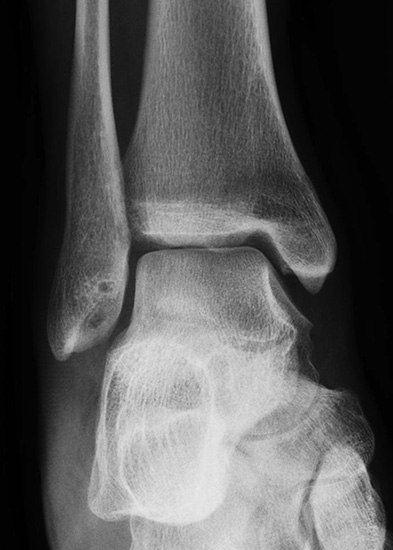

- Röntgenaufnahme des OSG in 2 Ebenen (seitlich und Mortiseview).

- MRT des OSG zur Beurteilung des ligamentären Schadens und möglicher Knorpelläsionen.

- Ggf. CT zur Bestimmung der Lage und Größe begleitender Osteophyten oder freier Gelenkkörper, sofern diese als Begleitpathologien vorliegen.